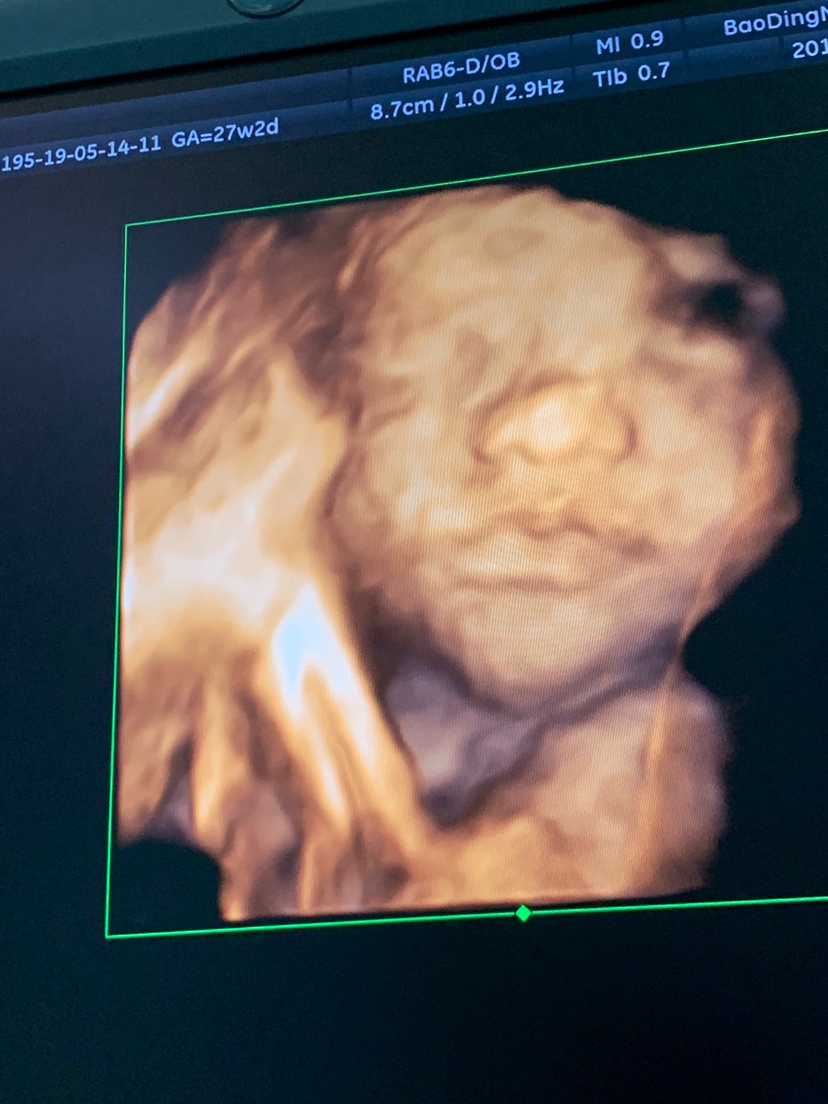

孕36周+6天

眼睛好像睁开了